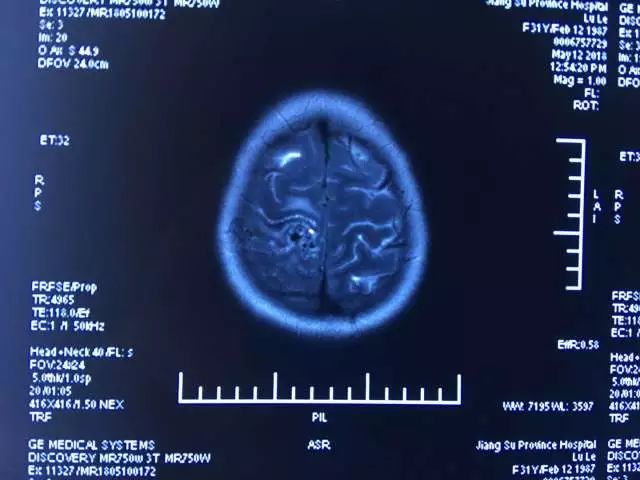

▲ 术前DSA

"看了她的片子,我认为有机会开刀",吴伟表示,并非所有的脑功能区血管畸形皆不可治,脑功能区血管畸形也并非手术切除后完全会影响功能,"还是要具体问题具体分析"。